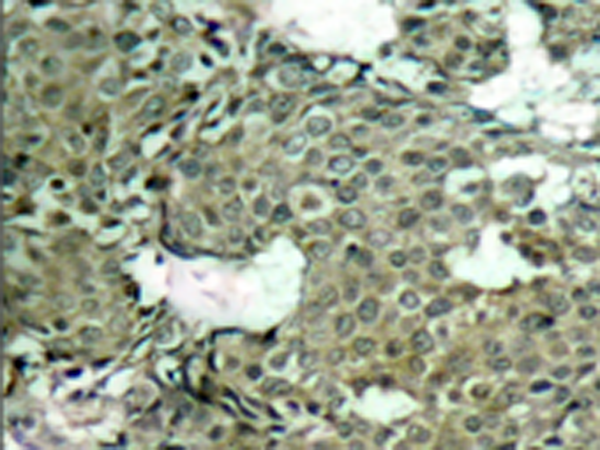

IHC positive control:

Human breast carcinoma

IHC Recommend dilution:

50-100